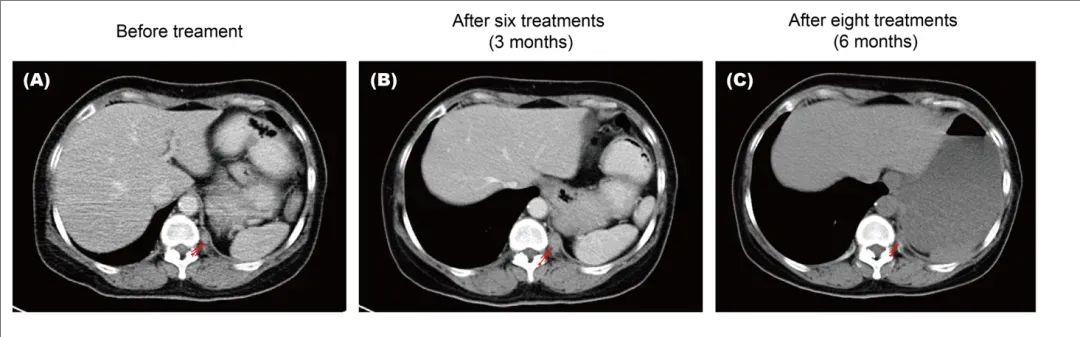

值得一提的是,其中1例肺癌患者(即#6患者),在接受同种异体γδ T细胞治疗前,计算机断层扫描(CT)显示已发生了肺癌腹腔内转移。经过经过6次(B)和8次(C)同种异体δ T细胞治疗后,与之前的腹部CT扫描相比,,左侧后侧未观察到新的可见病变(详见下图)。

▲图源“PMC”,版权归原作者所有,如无意中侵犯了知识产权,请联系我们删除

注:红色箭头显示:下纵隔左侧后侧肿大的淋巴结(a)。